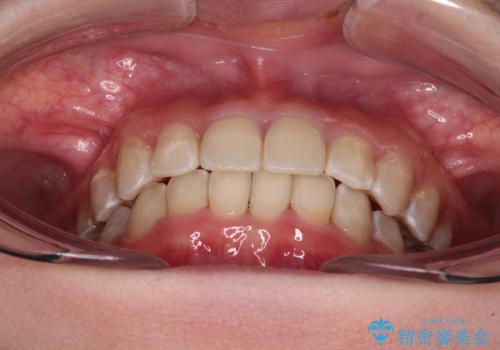

- 犬歯のクロスバイトを気にして来院された患者様です。

犬歯は歯根が太くて長いため、クロスバイトを改善するのは大変であることが多いですが、比較的スムーズに改善することができました。

インビザラインであったら、もっと期間はかかっていたような印象です。